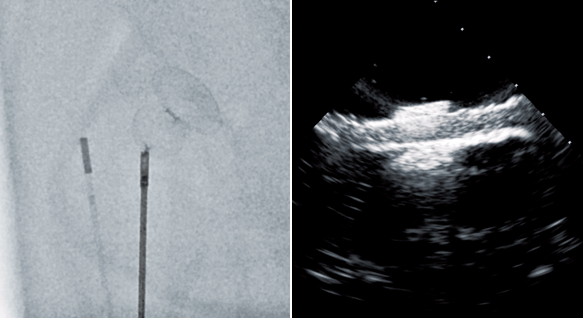

X線透視下、ならびに経食道エコーガイド下に、経⽪的⼼房中隔⽋損閉鎖術(ASD Closure: Atrial Septal Defect Closure)のシミュレーションを行うことが可能です。

欠損孔の大きさは標準で直径12mmにしてあります。サイジングバルーンで至適サイズのプラグを選択し、X線透視下にデリバリーカテーテルを左房内へ進め、経食道エコーガイド下に留置位置を確認しながら左⼼⽿内に閉塞⽤プラグを留置するという一連の⼿技を⾏うことができます。拍動ポンプで⾎流が再現されており、カテーテルを用いて造影を行うことも可能です。

TEE対応ワイドタンク

経食道エコーに対応したタンクです。X線透視下、非透視下での視認性を考慮した透明アクリルタンクです。